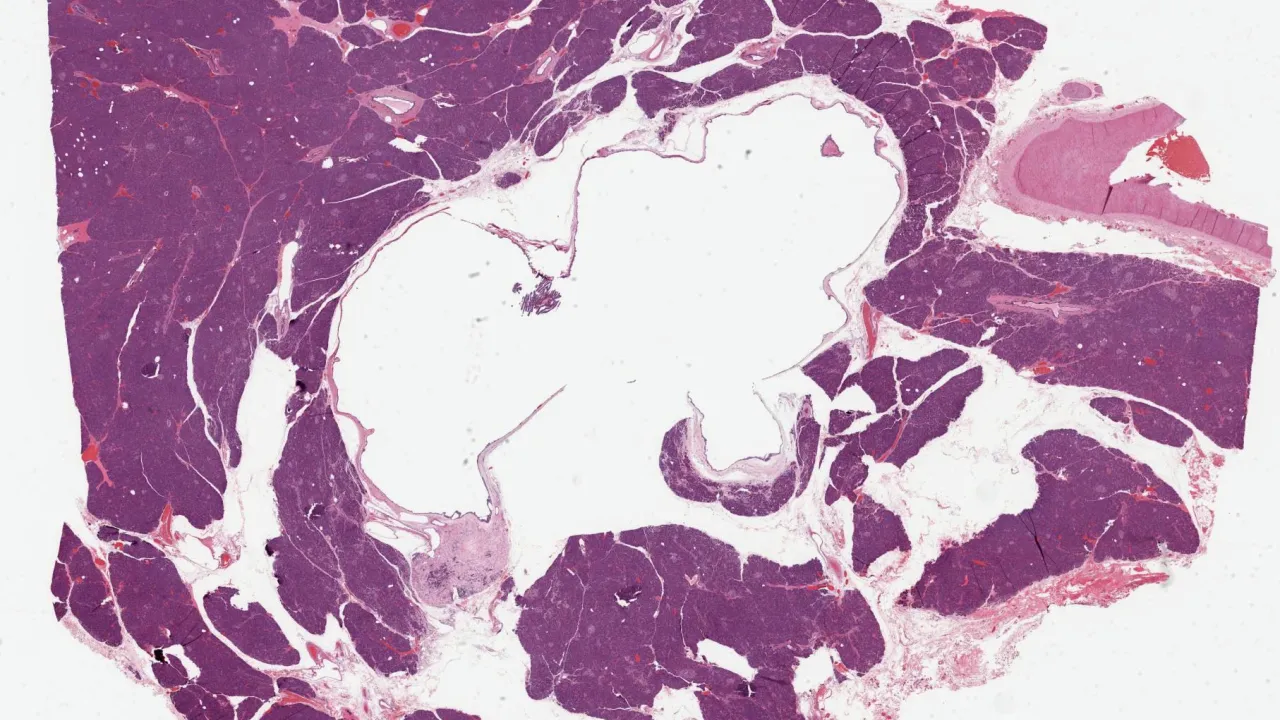

Pancreas, Mucinous cystic neoplasm, low grade